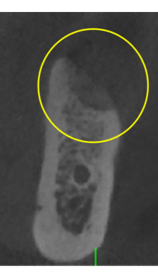

抜歯のう胞摘出

Perio Wave+Er:YAGレーザー+コールドレーザーで治療した箇所の経過です。

左から直後、1ヶ月経過時、2ヶ月経過時の画像です。

骨再生の確認をした際の動画です。

画像をクリックすると、youtubeにジャンプします。

骨再生

骨再生した箇所にインプラントを埋入します。

CTで治療計画を綿密に練ったうえで行いました。